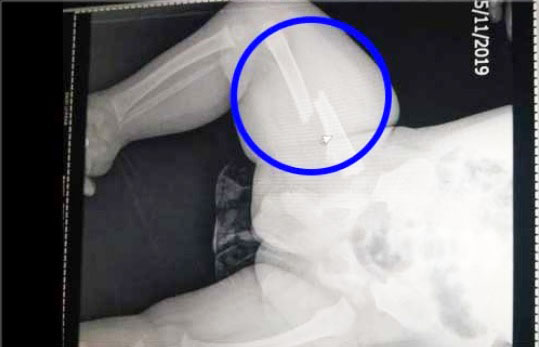

Como o estado de saúde da criança se agravou, ela deu entrada na última segunda-feira na Unidade de Pronto Atendimento (UPA) de Austin. A vítima foi atendida e após fazer exame de raio-x os médicos descobriram que ele estava com uma fratura no fêmur.

O bebê imediatamente foi encaminhado ao Hospital Geral de Nova Iguaçu (HGNI) onde está internado com estado de saúde estável após passar por cirurgia na passará por uma cirurgia na última terça-feira.

O HGNI infomou que o bebê estava com sinais de agressão na perna e um pequeno corte no lábio. Na unidade ele foi avaliado por pediatras e ortopedistas. A equipe do Serviço Social e o Conselho Tutelar do município estão acompanhando o caso. Este foi o sexto caso de agressão à menores atendido pelo HGNI este ano.